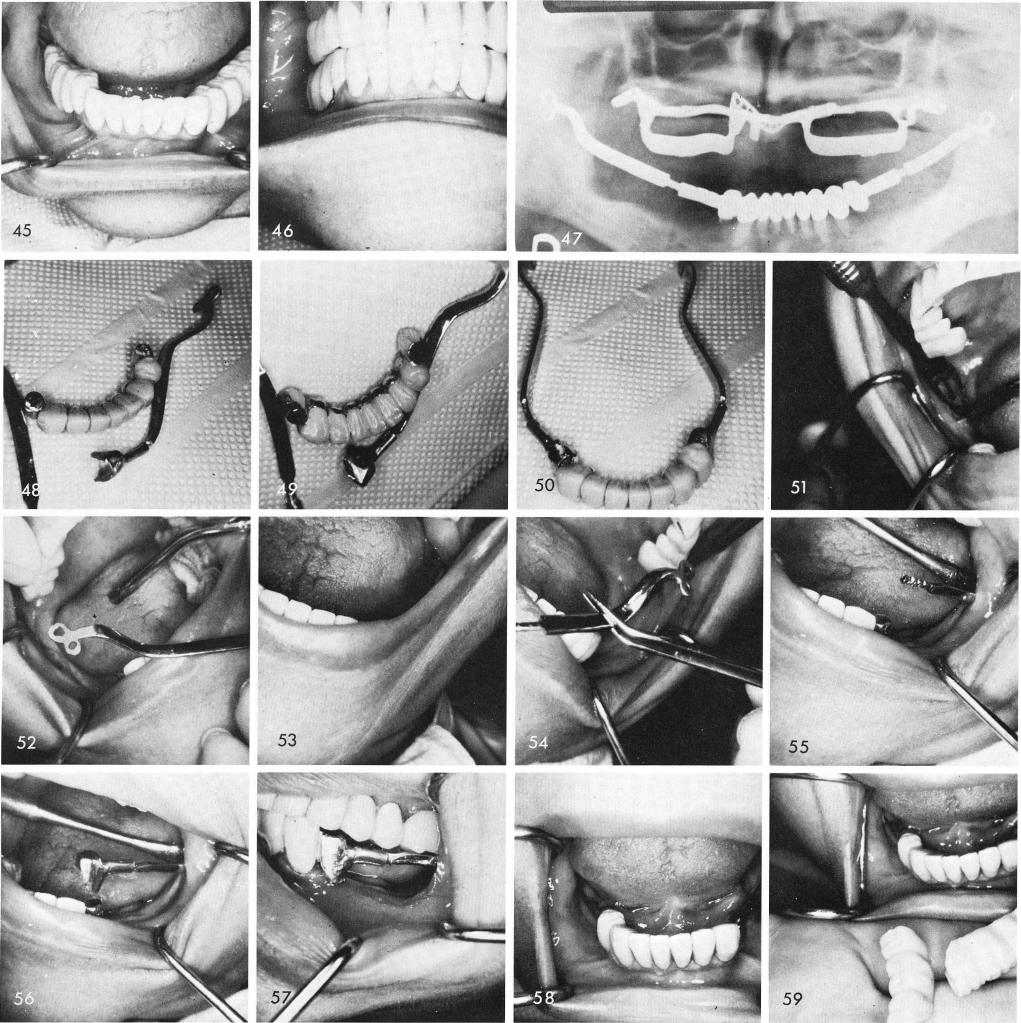

Another case showing the anterior prosthesis which must be completed before the posterior surgery can begin, figs. 48, 49, 50. The ramus groove is made and the blade is inserted, figs. 51, 52, and repeated on the opposite side, figs. 53, 54, 55. The telescopic coping with its hollow tube is fitted over the cable and can slide mesially and distally as it is tapped downward to en-gage the cantilevered pontic, figs. 56, 57. It is repeated on the other side, fig. 58, and the posterior quadrants are completed, figs. 59, 60, 61. The post-operative x-ray shows the reason why a sliding cable was used on the right side so as not to involve the broken, buried blade that had been functioning successfully five years prior to its breakage, fig. 62.

1 Sliding cable avoiding broken blade mandibular implant involvement